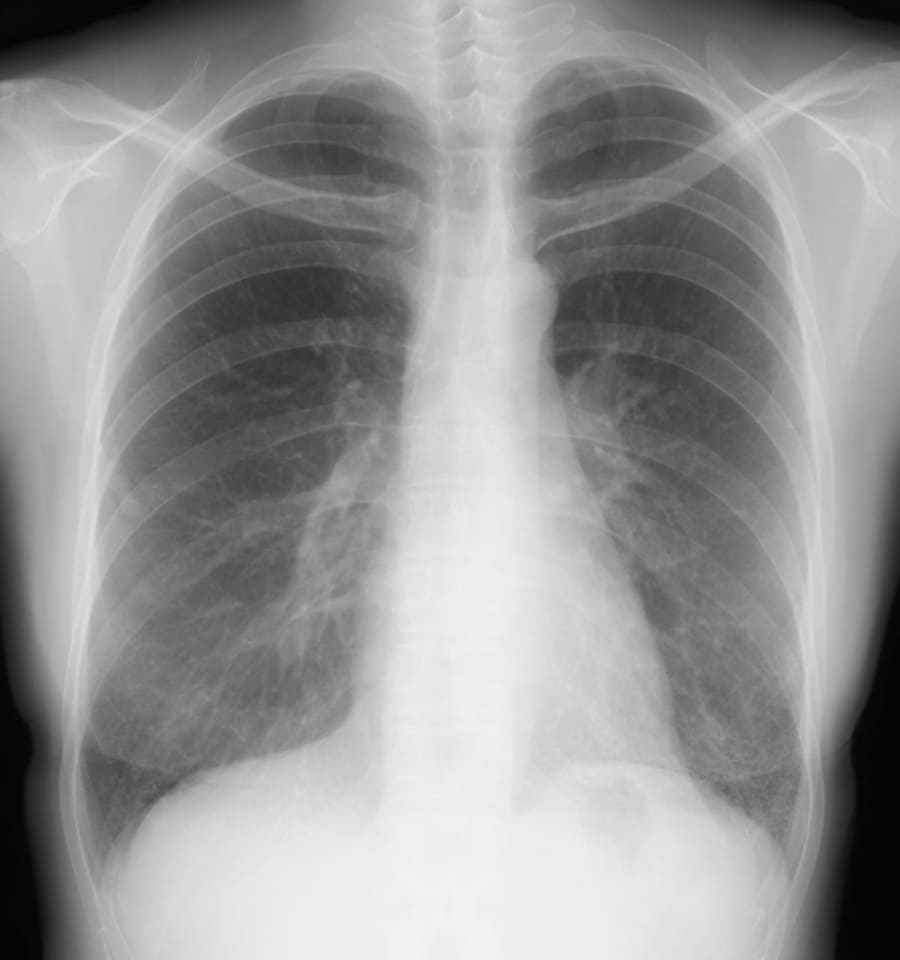

- Q1 胸部異常影を指摘された自覚症状のない40代女性

胸部異常影を指摘された自覚症状のない40代女性

この症例の病理パターンは?

DATA 1| X 線検査結果

びまん性の肺胞隔壁の線維性肥厚、軽度のリンパ球・形質細胞浸潤をみとめ、fibrotic NSIPの病理診断。

抗ARS抗体、抗SS-A抗体陽性であり、膠原病科にコンサルテーションしたものの、明らかな膠原病の所見はなく、特発性間質性肺炎の範疇である。

HRCTでは一見、非区域性に胸膜に接して広がる網状変化で、NSIPには特徴的でない(典型例は胸膜直下をスペアして気管支血管束に沿って広がる)。しかし、横隔膜直上では変化が軽微で、局在的には微細網状変化で均質性があり、NSIPの特徴も有し、生検が必要な症例である。